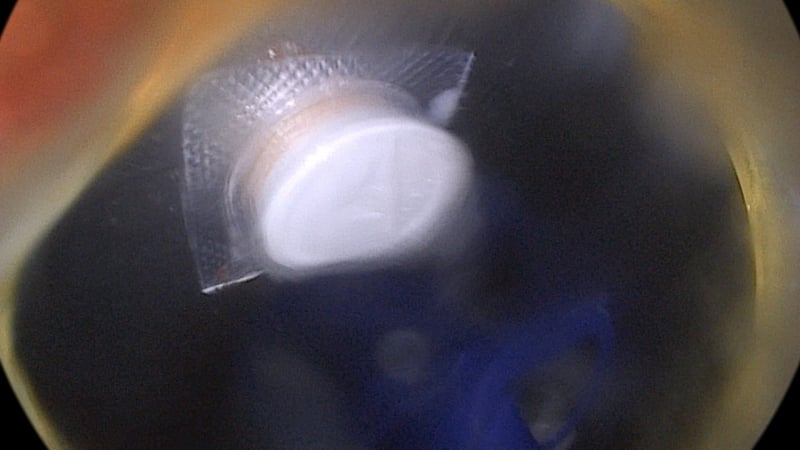

Tại Trung tâm Cấp cứu và Vận chuyển 115, bệnh nhân được thăm khám, chẩn đoán dị vật đường tiêu hóa và chỉ định nội soi can thiệp gắp dị vật. Kết quả nội soi cho thấy tại đoạn 1/3 trên của thực quản, ngay sát cơ thắt trên, có dị vật là viên thuốc còn vỏ, cạnh sắc, kích thước khoảng 1,5cm, gây trầy xước niêm mạc thực quản.

Kíp nội soi của Khoa Thăm dò chức năng đã tiến hành gắp dị vật qua nội soi bằng dụng cụ chuyên dụng. Thủ thuật diễn ra thuận lợi, dị vật được lấy ra an toàn. Kiểm tra sau can thiệp ghi nhận niêm mạc thực quản có vết xước nông, không chảy máu, không có dấu hiệu thủng.